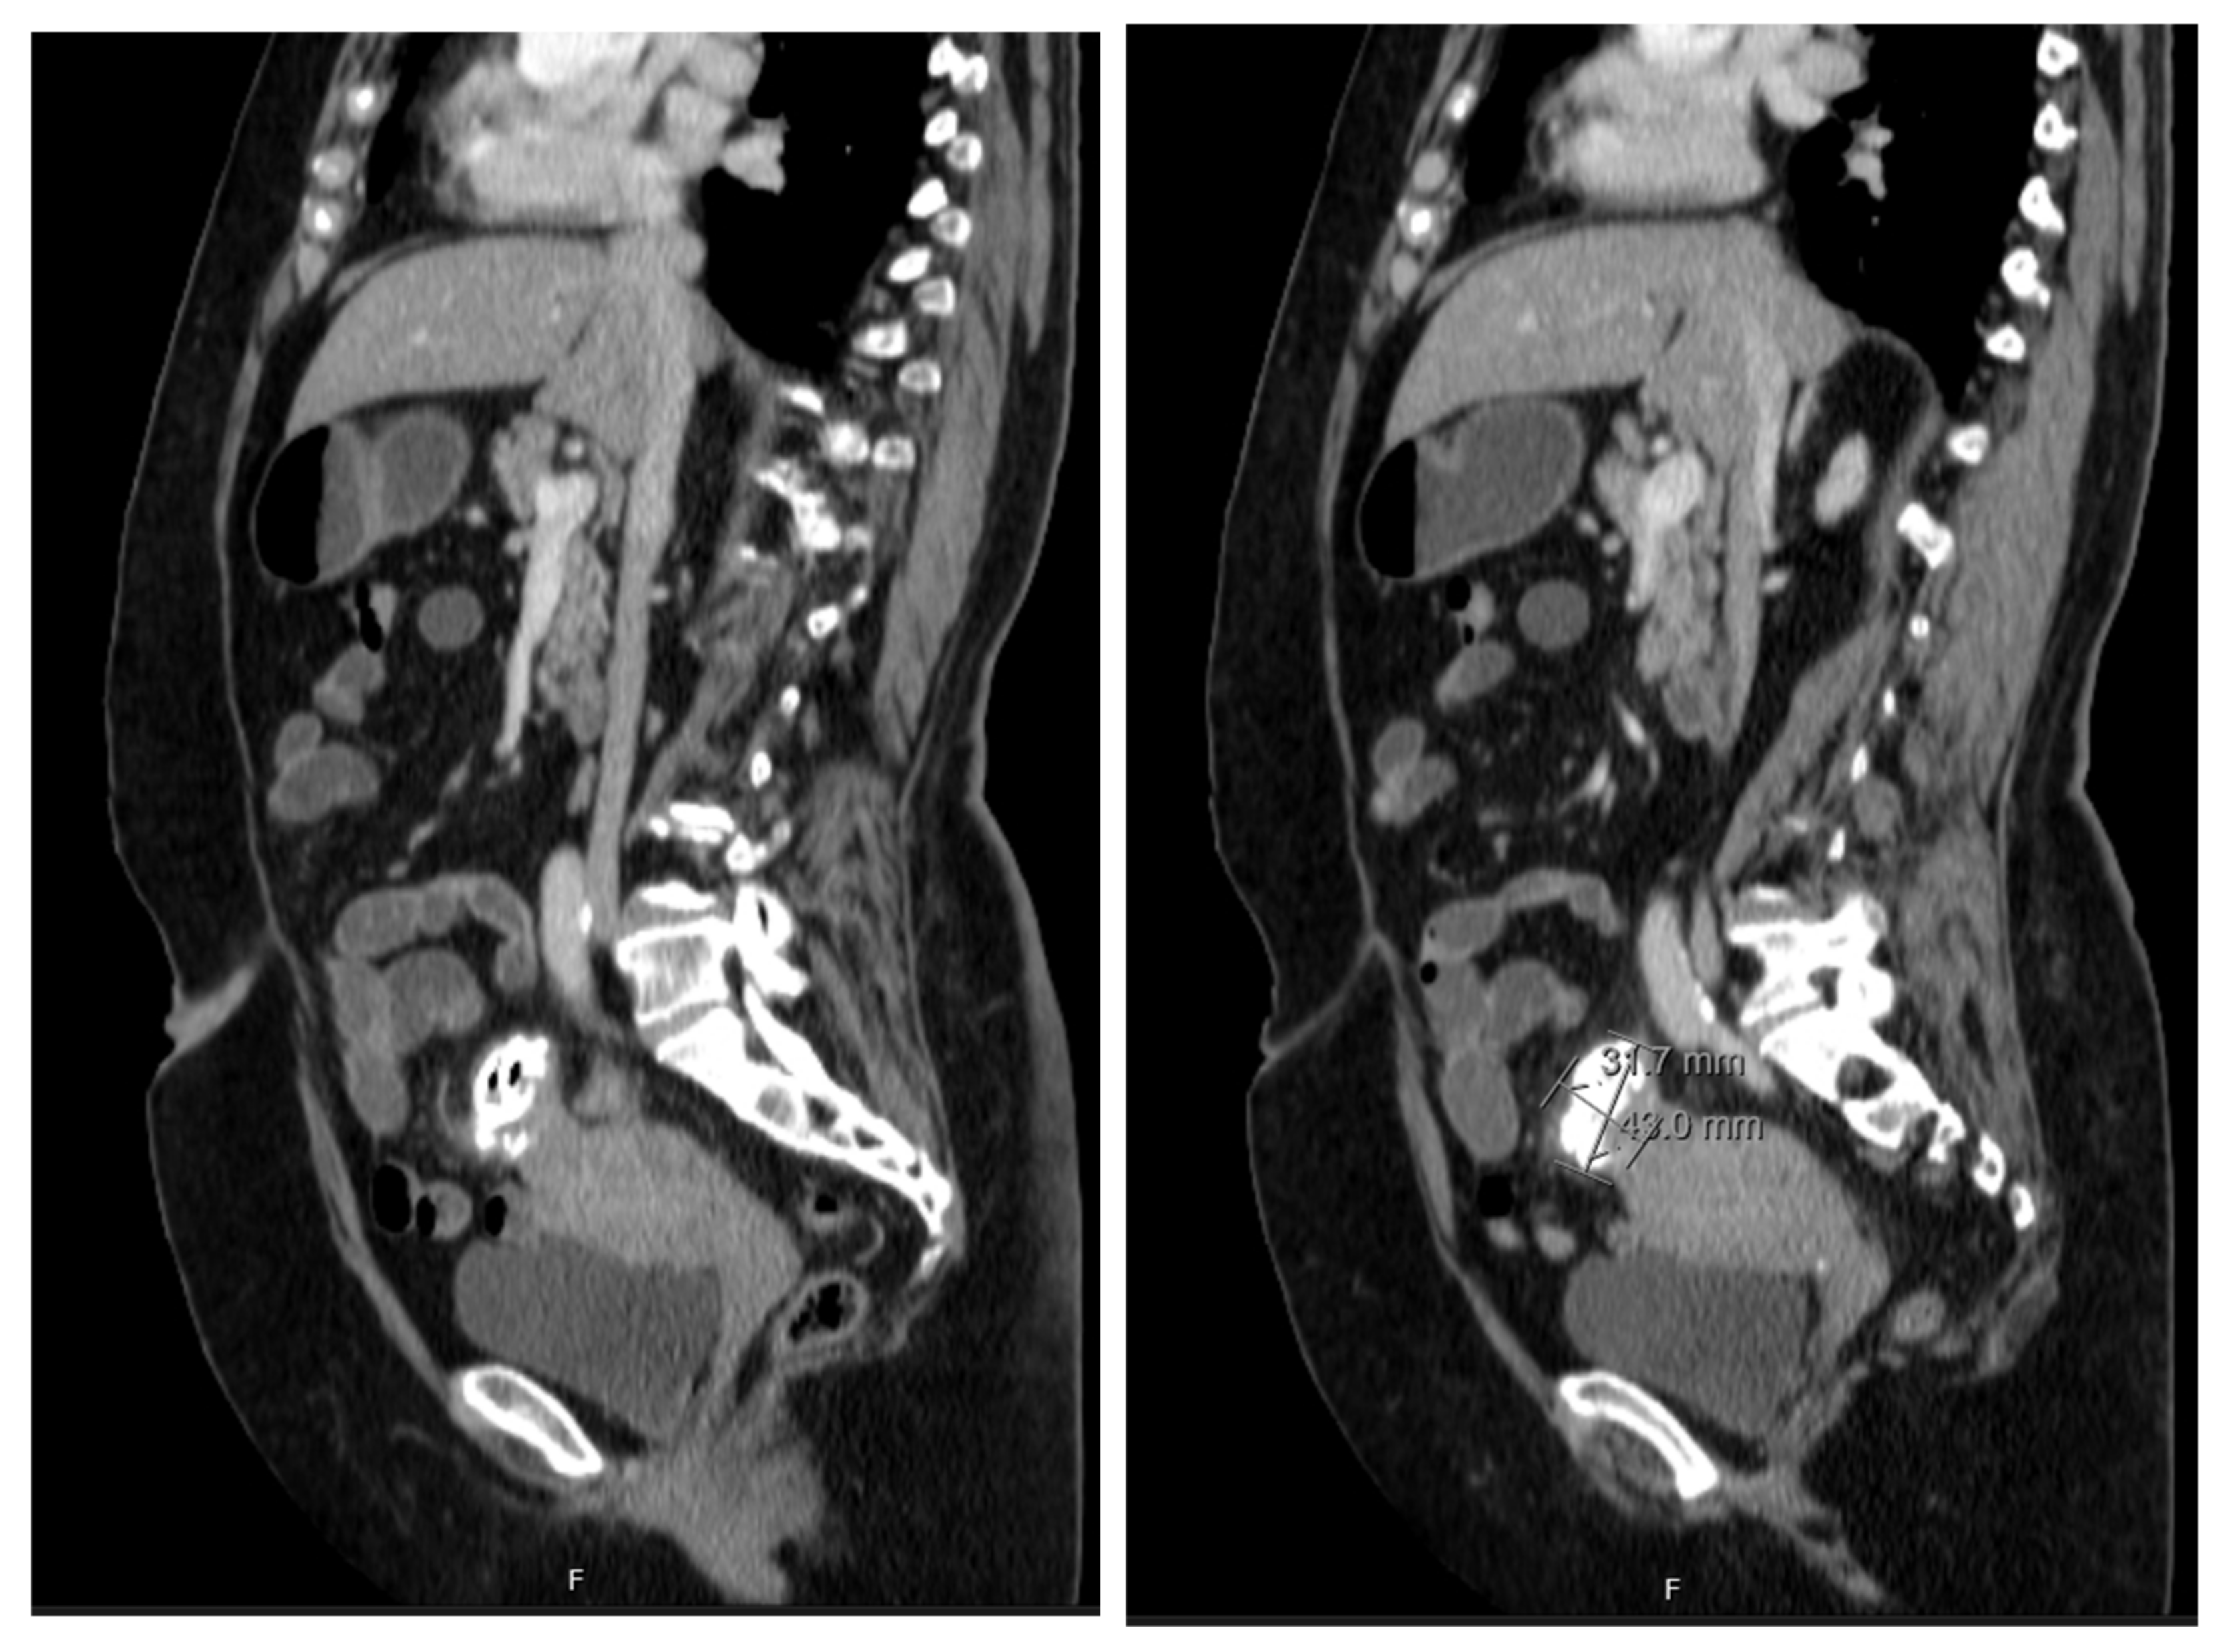

The patient underwent a Computed Tomography (CT) Enterography requested by the gastroenterologist. This exam showed a mass adjacent to the uterine fundus and in continuity with the sigmoid colon wall, with a nodular and exophytic appearance, dimensions of 3.4 × 3.2 × 4.3 cm, and identifiable calcifications and gas areas and conditioning a slight colonic retraction and fat enhancement in the surrounding area (Figure 2). The blood examinations and serum tumour markers (CA 125, CEA, and CA 19.9) were unremarkable.

Figure 2. CT enterography showing a nodular, exophytic, and extensively calcified formation with two gaseous points, with dimensions of 3.4 × 3.2 × 4.3 cm, in close proximity with uterine fundus and adjacent sigmoid colon and conditioning a slight colonic retraction and surrounding fat enhancement.